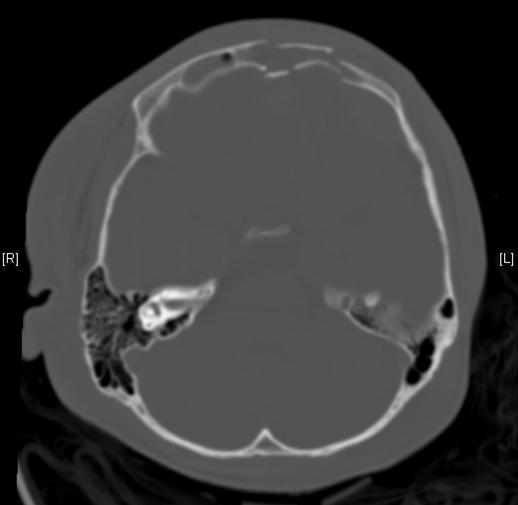

Dens Fracture Ct Dens Fracture X Ray Odontoid fractures are relatively common fractures of the c2 (axis) dens that can be seen in low energy falls in elderly patients and high energy traumatic injuries in younger. Mri is a valuable imaging modality for the diagnosis and evaluation of odontoid (dens) fractures due to its detailed visualization of bone marrow and assessment of supporting. The odontoid process fracture. Dens Fracture X Ray.

Dens Fracture Ct Dens Fracture X Ray The odontoid process fracture (also known as the peg or dens fracture) occurs where there is a fracture through the odontoid process of c2. Most dens fractures are caused by motor vehicle accidents and falls. Odontoid process fracture, also known as a peg or dens fracture, occurs where there is a fracture through the odontoid process. Mri is a valuable. Dens Fracture X Ray.